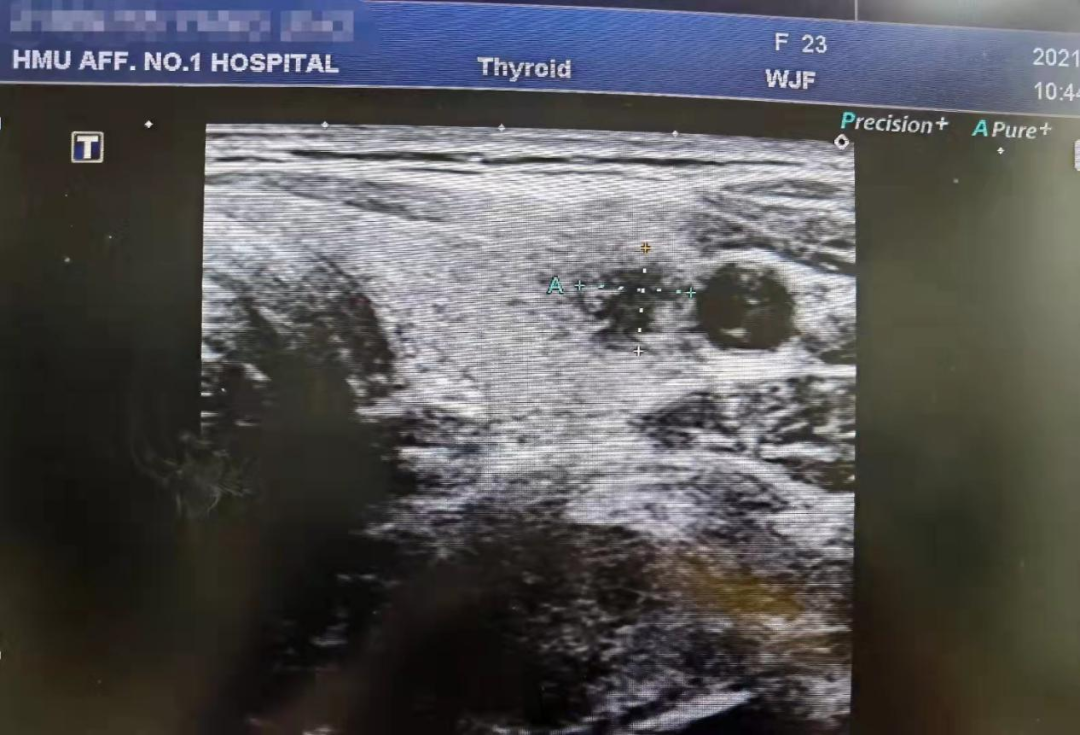

甲状腺是人体中非常重要的内分泌器官,外形像一只美丽的蝴蝶,通过分泌甲状腺激素促进物质和能量的代谢,对人体的多系统具有重要影响。近年来,随着人们体检意识的增强和超声诊疗技术的迅猛发展,甲状腺恶性结节的检出率呈逐年增高的趋势,而一旦确诊,颈部这只美丽的蝴蝶就面临着折翼的风险——外科手术切除。腺体切除、颈前瘢痕、终身服药像一幕幕阴霾,笼罩在患者的头上。 患者小Y是一个23岁年轻美丽的女孩儿,在哈医大一院超声医学科进行超声检查后,发现右侧叶有一枚大小约0.8cmx0.6cmx0.8cm的TI-RADS 4c类结节(图1),并且经过穿刺病理证实为甲状腺乳头状癌。这如同一个晴天霹雳般的坏消息,让这个女孩儿痛苦不已。如果选择手术切除,术后颈部的瘢痕、终身服药的不便、尚未结婚怀孕的现实难题,让小Y难以接受传统手术疗法。在了解到她的困扰后,哈医大一院超声医学科介入团队迅速启动科内会诊及病例讨论机制,在学科主任吴长君教授的提议下,决定采用超声引导下的射频消融治疗,对小Y的恶性结节进行局部灭活,并且尽可能保留正常腺体。通过术前审慎评估,细致准备,消融手术由超声医学科王俊峰副教授主刀。在实时超声的引导下,射频消融针精准的进入恶性病灶内,仅用时3分钟左右,消融范围就完全覆盖病灶(图2)。 治疗过程中,超声介入团队配合默契,采用多种技术保障患者安全,避免了甲状腺周围重要组织(血管、神经)的损伤。治疗取得了圆满成功。术后,小Y开心的笑了,超声介入团队也由衷的为她感到高兴(图3)。 哈医大一院超声医学科主任、博士生导师吴长君教授介绍,超声引导下射频消融治疗甲状腺乳头状癌,具有非常多的优点。在保障治疗效果的同时,可以满足患者个性化的需求。射频消融用时短,术后恢复快,无需终身服药,并且避免了颈部瘢痕,尤其对于爱美女性及拒绝终身服药的患者非常友好,是一种值得大力推广和应用的治疗技术。哈医大一院超声医学科介入团队秉承不断进取、精益求精的理念,着力打造甲状腺疾病诊疗一体化平台,为守护龙江人民的健康不懈努力!